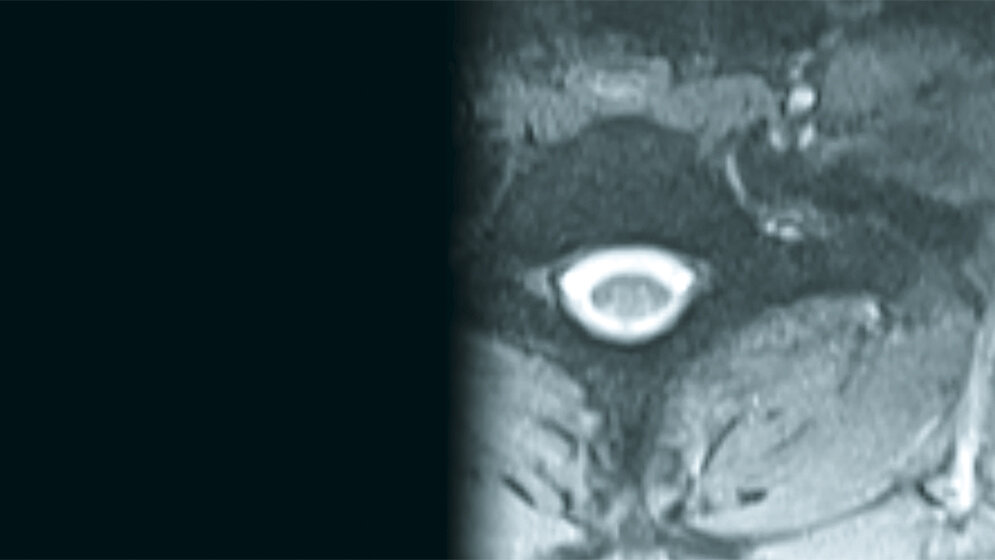

Spinale Malformationen: Stummelrippen und Querfortsatzanomalie der Halswirbelsäule

Das Skelettsystem kann verschiedene Varianten und Malformationen aufweisen, die in ihrer klinischen Bedeutung variabel sind. Neben symptomatisch stummen Veränderungen können auch funktionelle Beeinträchtigungen, Schmerzen oder auch Beeinträchtigungen anderer Organe vorkommen.

Die Inzidenz der zahlenmäßig varianten Rippenanlagen beträgt 6,3 %. Bei isoliertem Vorkommen handelt es sich um Normvarianten. Zervikale Rippen kommen bei etwa 2 % der Population vor. Sie sind in der Differenzialdiagnose bei supraklavikulären Raumforderungen zu berücksichtigen.